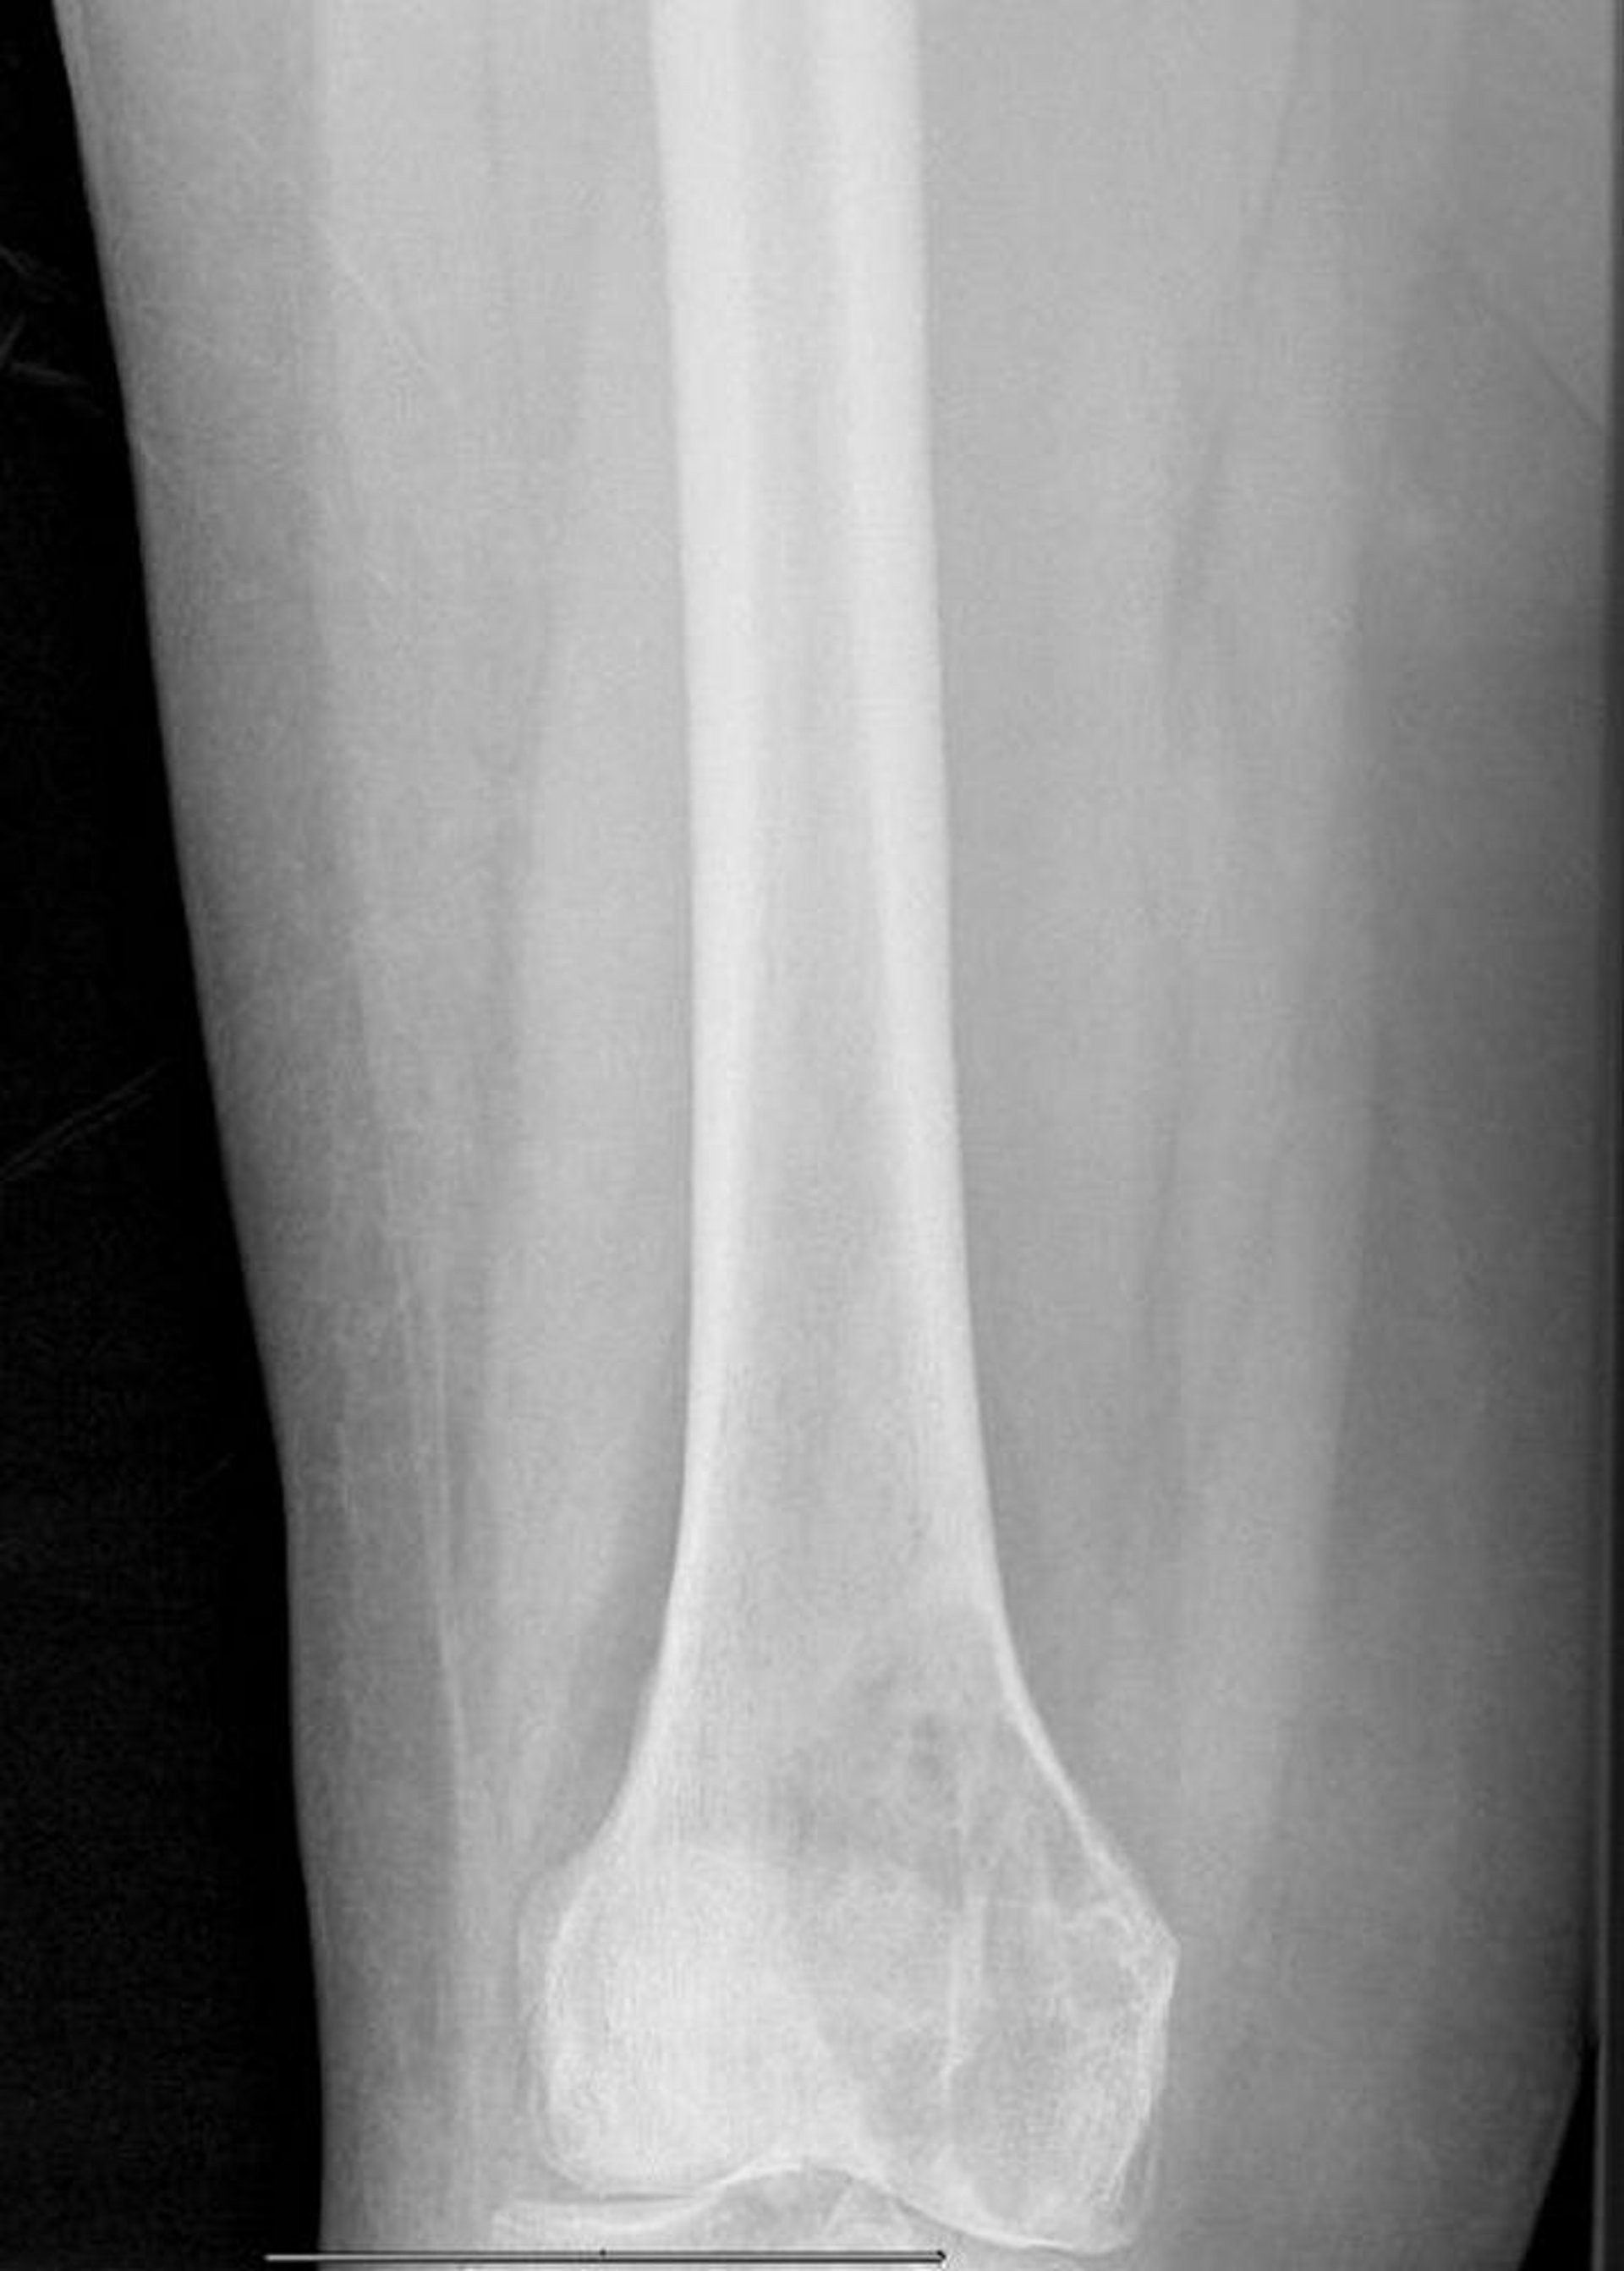

Lytische Metastasen im distalen Femur

Dieses Röntgenbild zeigt eine große metastatische lytische Läsion des medialen Femurkondylus mit drohender pathologischer Fraktur.